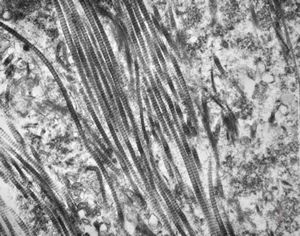

M, 43y. | myeloid leukemia … Auer bodies